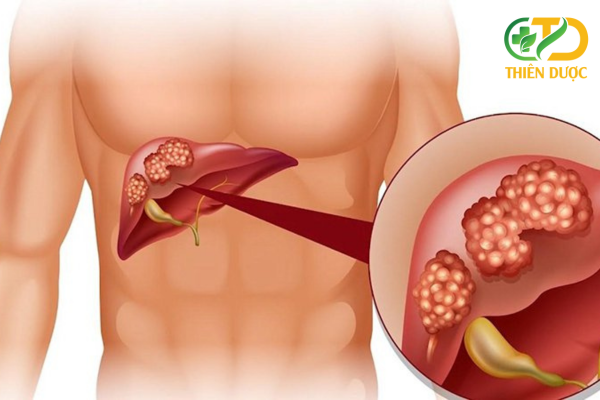

Viêm gan C là một bệnh truyền nhiễm do virus viêm gan C (HCV) gây ra. Virus này tấn công vào gan, gây ra tình trạng viêm gan, có thể dẫn đến tổn thương gan mãn tính, xơ gan và ung thư gan.

Mục tiêu chính của điều trị viêm gan C là loại bỏ virus HCV hoàn toàn khỏi cơ thể. Việc này giúp ngăn ngừa tiến triển thành xơ gan, ung thư gan và cải thiện chức năng gan.

- Mức độ tổn thương gan: Giai đoạn xơ gan càng nặng, việc điều trị càng khó khăn hơn.